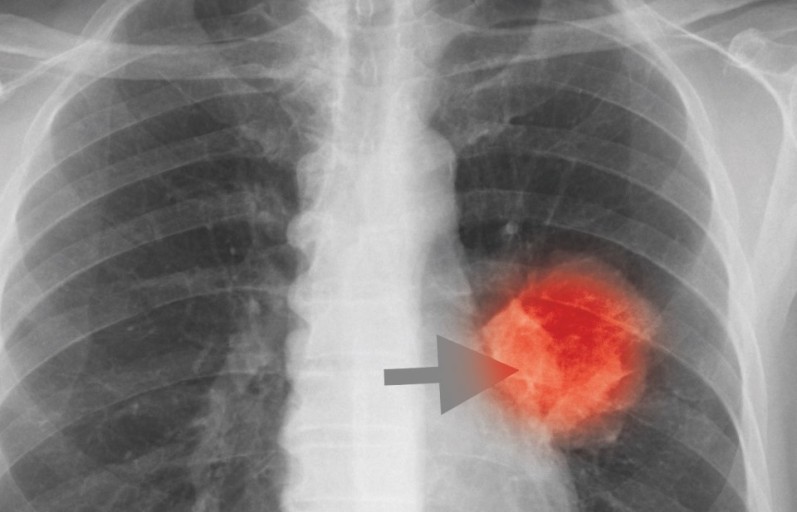

폐암 초기증상 - 가래에 피가 섞여 나옴 (객혈)

- 설명: 기침과 함께 피가 섞인 가래나 피 덩어리가 나오는 증상입니다. 암세포가 기관지 점막의 혈관을 침범하여 손상시키면서 발생합니다. 가래에 묻어 나오는 정도부터 덩어리진 피가 나오는 경우까지 다양합니다. 소량이라도 객혈이 나타나면 즉시 병원을 방문해야 합니다.

- 정기적인 건강 검진: 위와 같은 증상이 하나라도 나타나면 즉시 병원을 방문하여 흉부 X-ray, CT 촬영 등 검사를 받는 것이 중요합니다.